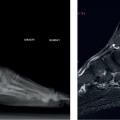

Radiographies standard bilatérales et comparatives face et profil en charge pour détecter enthésophyte (épine) rétro- et/ou sous-calcanéen (fig. 2 ), érosion osseuse éventuelle, trouble statique, calcifications, malformation du calcanéum.

– radio de profil : enthésophyte sous-calcanéen ; pas d’érosion ; à l’échographie : aponévrose plantaire superficielle épaissie et hypo-échogène à son insertion proximale ; l’IRM confirme l’épaississement et l’absence de complication (fissure ou rupture associée).2